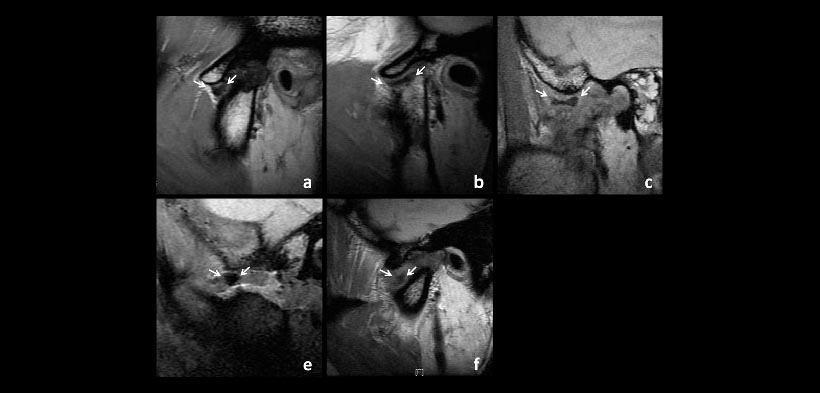

Fig.3 La forma de disco lateral en la anquilosis Tipo A2. (A) Hemiconvexo, (b) biplanar, (c) bicóncava, (d) biconvexa, (e) amorfo. Las flechas indican el disco